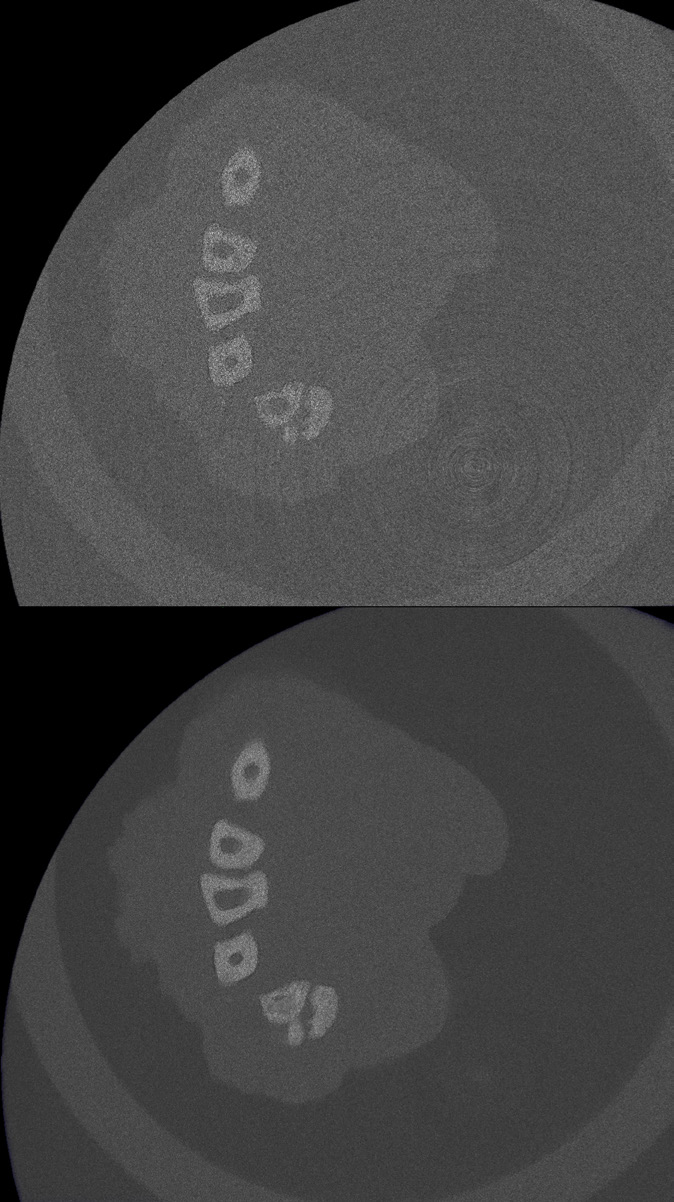

標準的なビームハードニング補正に加えて、独自の統合型Active Ring Reduction(ARR)ハードウェアを新しく搭載し、リング状のアーチファクトを自動的に取り除き、画像品質を向上させています。

- Active Ring Reduction - リング状のアーチファクトを自動で除去